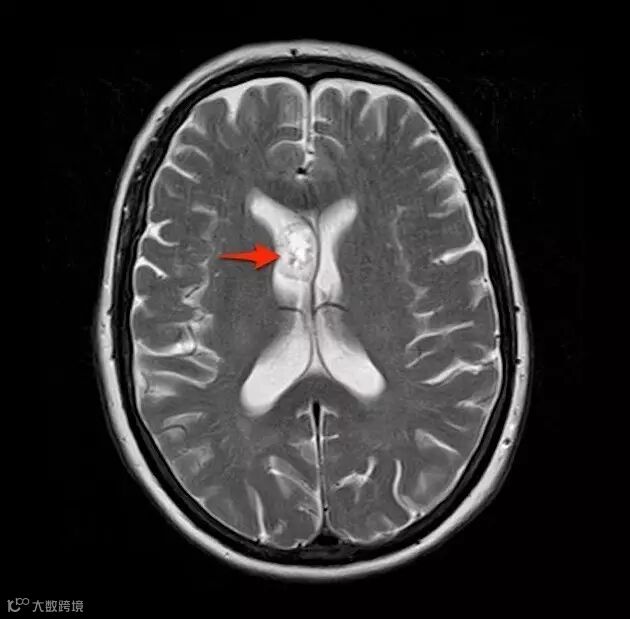

T2WI